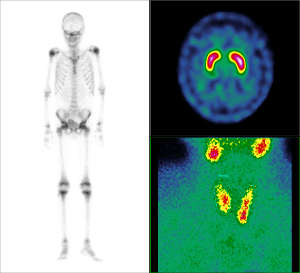

Scintigrafické vyšetrenia

Scintigrafia skeletu, kostnej drene, scintigrafia zápalových lézií, lymfoscintigrafia končatín, lokalizácia sentinelovej LU, scintigrafia prištitných teliesok (MIBI), diagnostika Parkinsonovej choroby a DLB (DaTSCAN), mapovanie sympatikovej inervácie myokardu (MIBG), scintigrafia amyloidózy myokardu, rovnovážna rádionuklidová ventrikulografia (MUGA), scintigrafia heparu na dif dg. hemangiómu